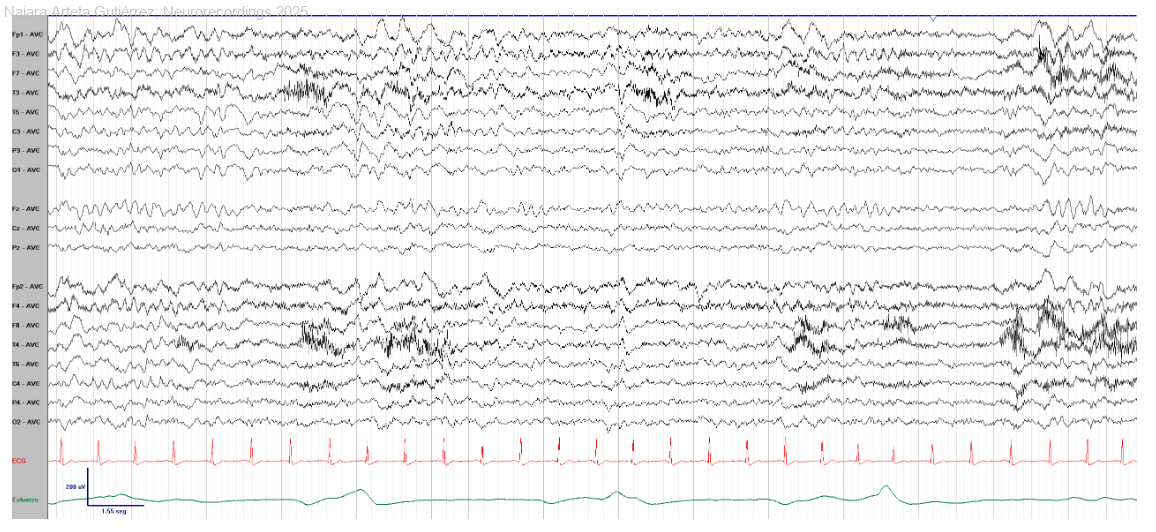

Hombre | 72 años

Diagnóstico final: Encefalitis herpética por virus herpes simplex 1

Paciente que acude a urgencias por comenzar el día previo con alteración en la emisión y compresión del lenguaje. Desde hacía 3 días presentaba además debilidad generalizada e hiporexia. En la exploración neurológica se objetivan inatención,...